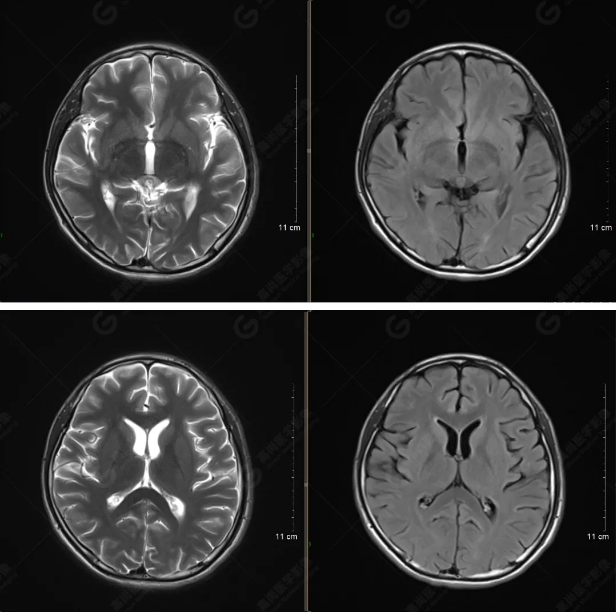

(左側(cè)為薄層原始圖像,右側(cè)為后處理5mm圖像)

SWI序列影像表現(xiàn)及診斷

左側(cè)額底及左側(cè)顳葉內(nèi)見多發(fā)斑點狀極低信號影??紤]額顳葉多發(fā)腦挫傷伴微出血、含鐵血黃素沉著,左側(cè)乳突骨折、乳突內(nèi)積血。討論:1、SWI利用不同組織間磁敏感的差異成像并將其放大,通過檢測病灶中的靜脈分布、出血灶和礦物質(zhì)沉積等,有效改善了相關(guān)疾病的診斷,主要應(yīng)用于中樞神經(jīng)系統(tǒng)。2、根據(jù)磁距圖像和相位圖像表現(xiàn),對于鑒別顱內(nèi)出血及鈣化有一定程度的價值,用于彌補(bǔ)MRI對鈣化顯示的不足。